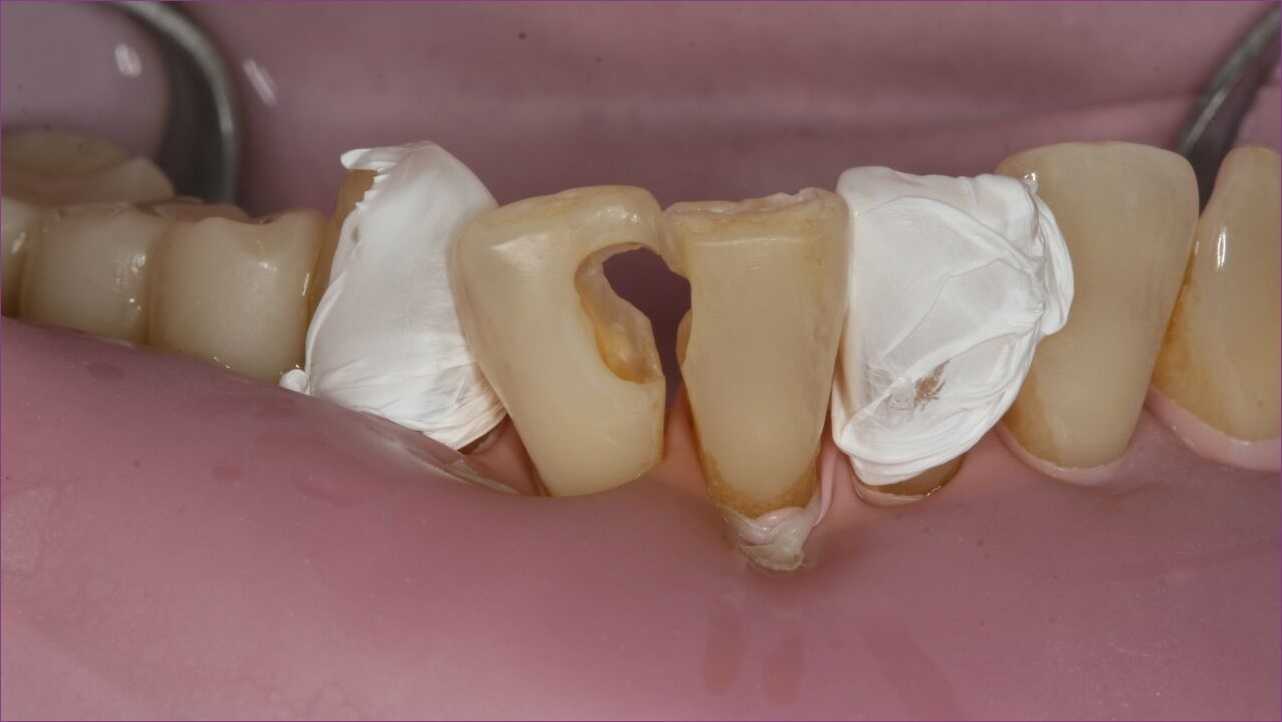

A kompozittömés manapság a legmodernebb és egyben legesztétikusabb tömésfajtának számít. Az anatomikus felépítésnek köszönhetően a fog eredeti funkciója teljes mértékben helyreállítható. A kezelést ezúttal úgynevezett kofferdamizolációban végeztük, mivel a korszerű tömések nagyon érzékenyek a nedvességre. A gondosan elhelyezett gumilepedő távol tartja a nyálat és az egyéb nedvességforrásokat a kezelt területtől. Ráadásul megakadályozza, hogy bármi a torokba kerüljön, például az apró amalgámdarabok.

Hölgypáciensünk roppant elégedett volt a végeredménnyel. Mint a képen is látható, gyakorlatilag eltüntettük a szuvasodás nyomait. Így derűs természetének ismét teret engedhet, vagyis bátran mosolyoghat!